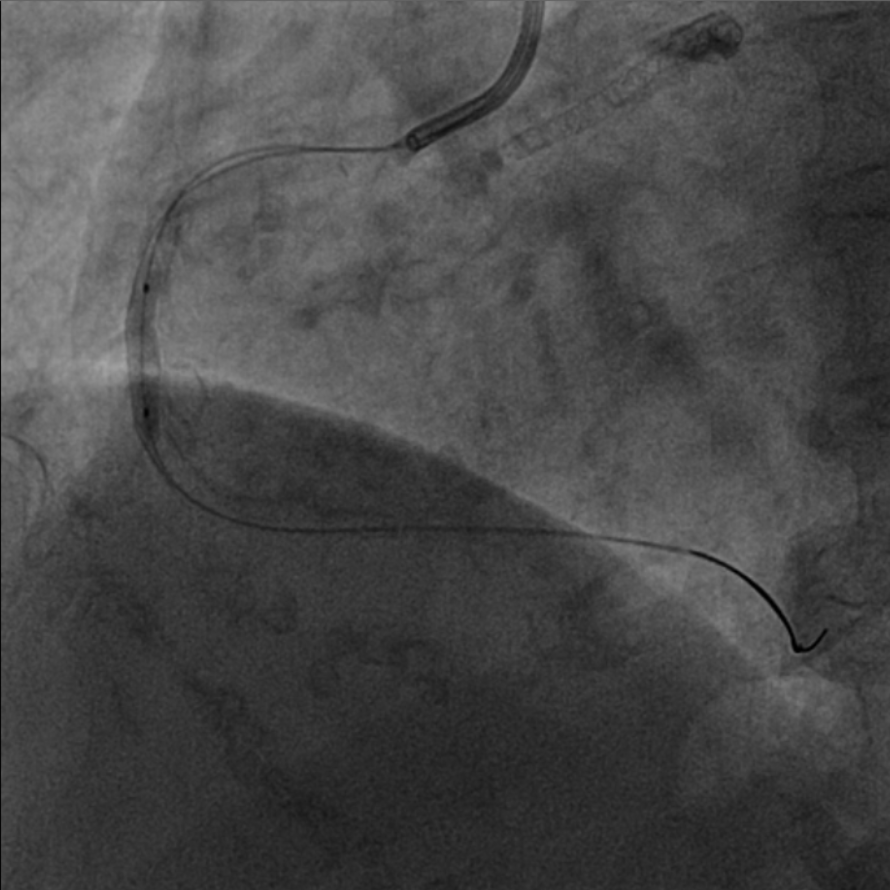

图4 3.0 Shockwave处理后可见钙化断裂 高压球囊验证膨胀良好

该患者入院后,完善相关检查并再次建议行CABG治疗,但家属仍拒绝,遂考虑再次行PCI手术干预。冠脉造影提示患者冠脉右冠状动脉中段70-95%再狭窄,左主干末端80%狭窄,前降支原支架中远段 80-95%再狭窄,回旋支完全闭塞,急需手术尽快解决冠脉血流灌注问题,否则随时有生命风险,但患者多处支架内/节段内再狭窄,造影提示钙化明显,外院已尝试无法扩张,经手术团队充分讨论后,计划在IABP支持下,先进行右冠状动脉干预,利用IVUS精准评估原支架再狭窄部位情况,采用旋磨或Shockwave冲击波球囊处理无法扩张的病变部位,右冠处理后择期进行左冠状动脉干预。在制定了详尽的手术计划后,手术团队首先对患者的右冠状动脉行IVUS检查,结果提示该患者右冠中段支架局部膨胀不良,局部支架面积6.67mm²,管腔内多处可见钙化小结及270°以上钙化,IVUS钙化积分达3分。由于膨胀不良处原支架后方可见钙化斑块,常规旋磨效果不佳,对于此类钙化病变,IVL处理是最佳方案。手术团队对近端采取棘突球囊及高压球囊进行扩张,采用Guidezilla辅助下输送3.0mmx12mm Shockwave冲击波球囊于右冠钙化处进行冲击波钙化斑块碎裂术,通过IVUS证实支架内的新生钙化病变得到松解,原膨胀不良部位支架面积达到7.76mm²,后经过高压球囊充分预处理,顺利完成右冠支架植入,术后复查右冠原膨胀不良部位支架面积9.17mm²。